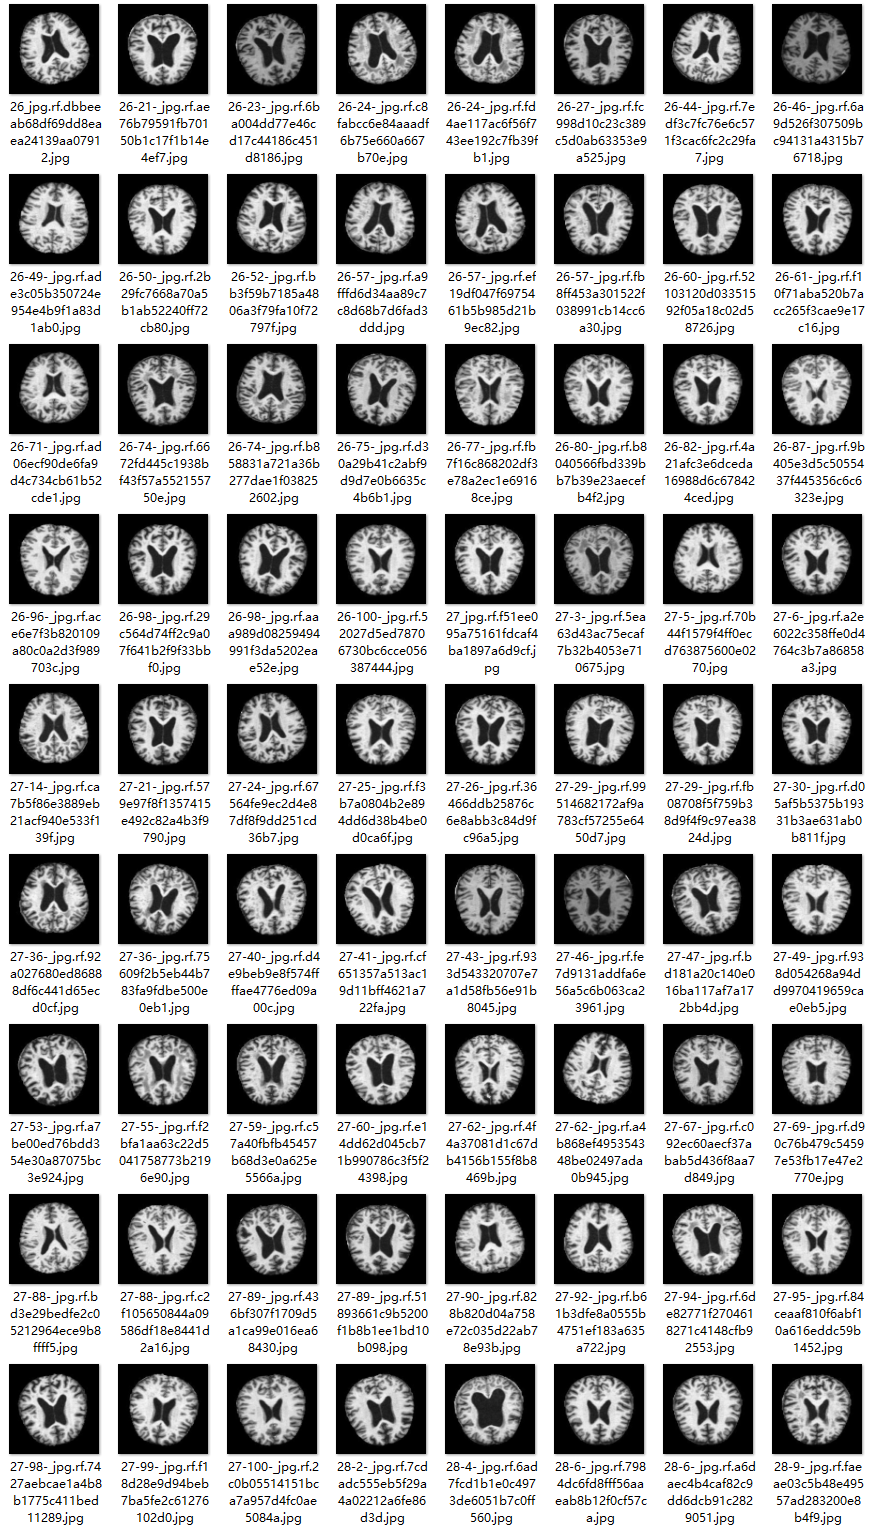

2.数据集准备与训练

本研究使用了包含各种阿尔兹海默症相关图像的数据集,并通过Labelimg标注工具对每张图像中的目标边框(Bounding Box)及其类别进行标注。然后主要基于YOLOv8n这种模型进行模型的训练,训练完成后对模型在验证集上的表现进行全面的性能评估及对比分析。模型训练和评估流程基本一致,包括:数据集准备、模型训练、模型评估。本次标注的目标类别为阿尔兹海默症,数据集中共计包含3288张图像,其中训练集占2572张,验证集占716张。部分图像如下图所示:

部分标注如下图所示: